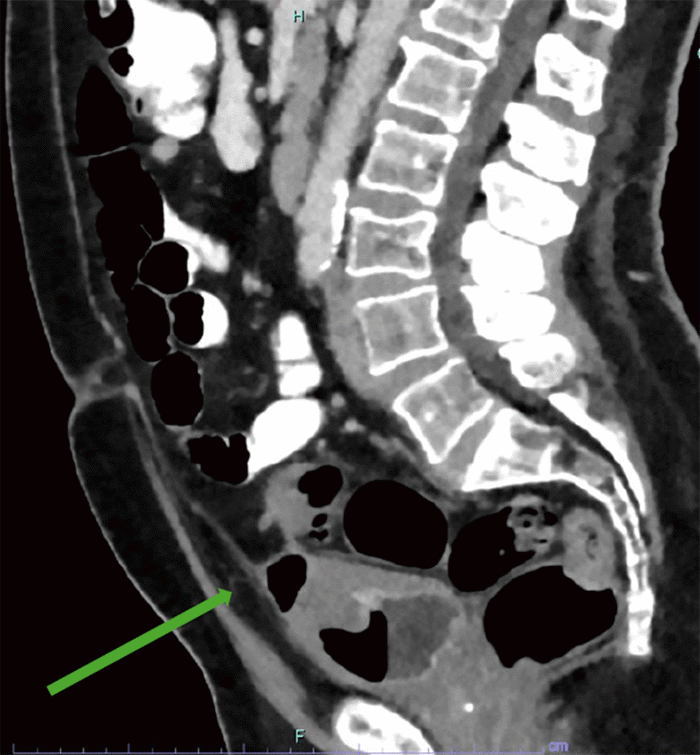

Initial evaluation via computed tomography (CT) of the abdomen and pelvis identified findings consistent with acute-on-chronic diverticulitis of the mid-sigmoid colon, without evidence of abscess or frank perforation. A mass-like inflammatory appearance at the dome of the bladder suggested a colo-vesical fistula, although a definitive fistulous communication between the inflamed colon and the bladder was not unequivocally visualized. Additionally, a prominent midline gas-filled outpouching was noted extending superiorly from the bladder dome into the prevesicular extraperitoneal space, consistent with a urachal remnant or diverticulum (Figure 1). The patient was diagnosed with a urinary tract infection and complicated diverticulitis and was discharged with a 10-day course of antibiotics, with referrals for outpatient follow-up with colorectal surgery and urology.

Figure 1. CT Demonstrating Urachal Remnant. Published with Permission

Axial CT scan of the pelvis. The image shows a gas-filled outpouching (green arrow) arising from the dome of the bladder and extending superiorly into the prevesicular extraperitoneal space, consistent with a urachal remnant